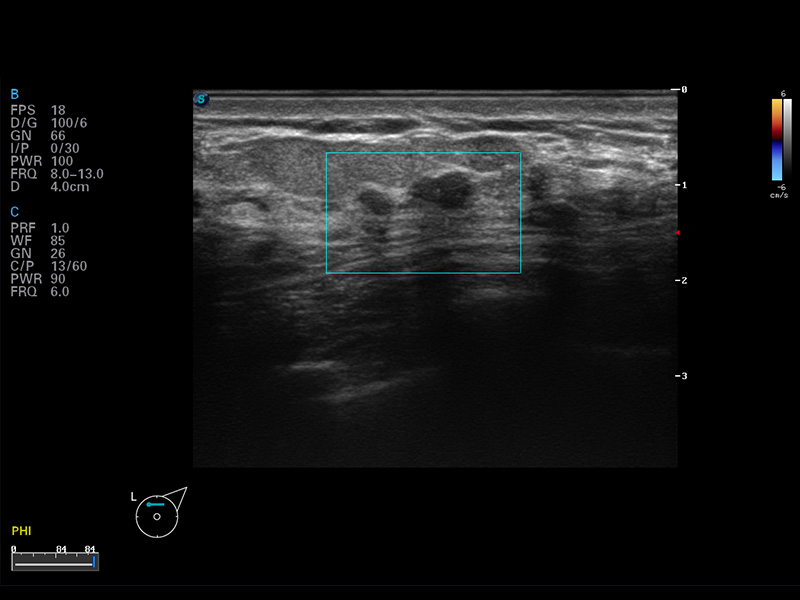

成像技术

μ-Scan微米成像

谐波成像

空间复合成像